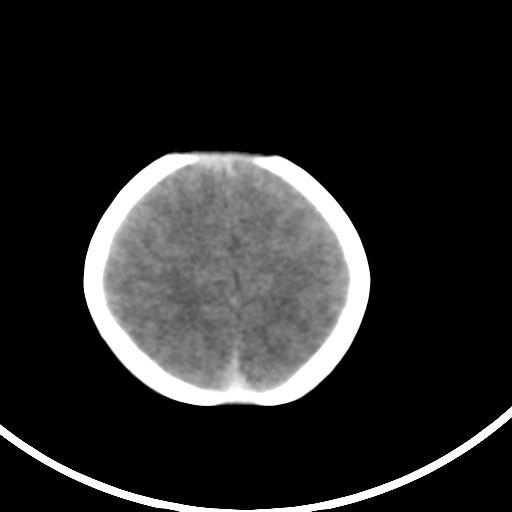

新生儿3天,超过预产期5天剖宫产,有缺氧病史,具体评分不详,现反应差,肌张力低,前囟平,原始反射存在,无苦闹等。

正常

颅底骨质影,正常颅脑表现。

颅底骨质影,正常颅脑表现.

正常颅脑表现。

kaolv小脑幕,后纵裂区蛛网膜下腔出血;轻度脑肿胀

支持9楼意见。

未见明显异常

矢状窦旁征——支持蛛网膜下腔出血

颅脑ct平扫未见异常。

新生儿正常颅内表现

sah。